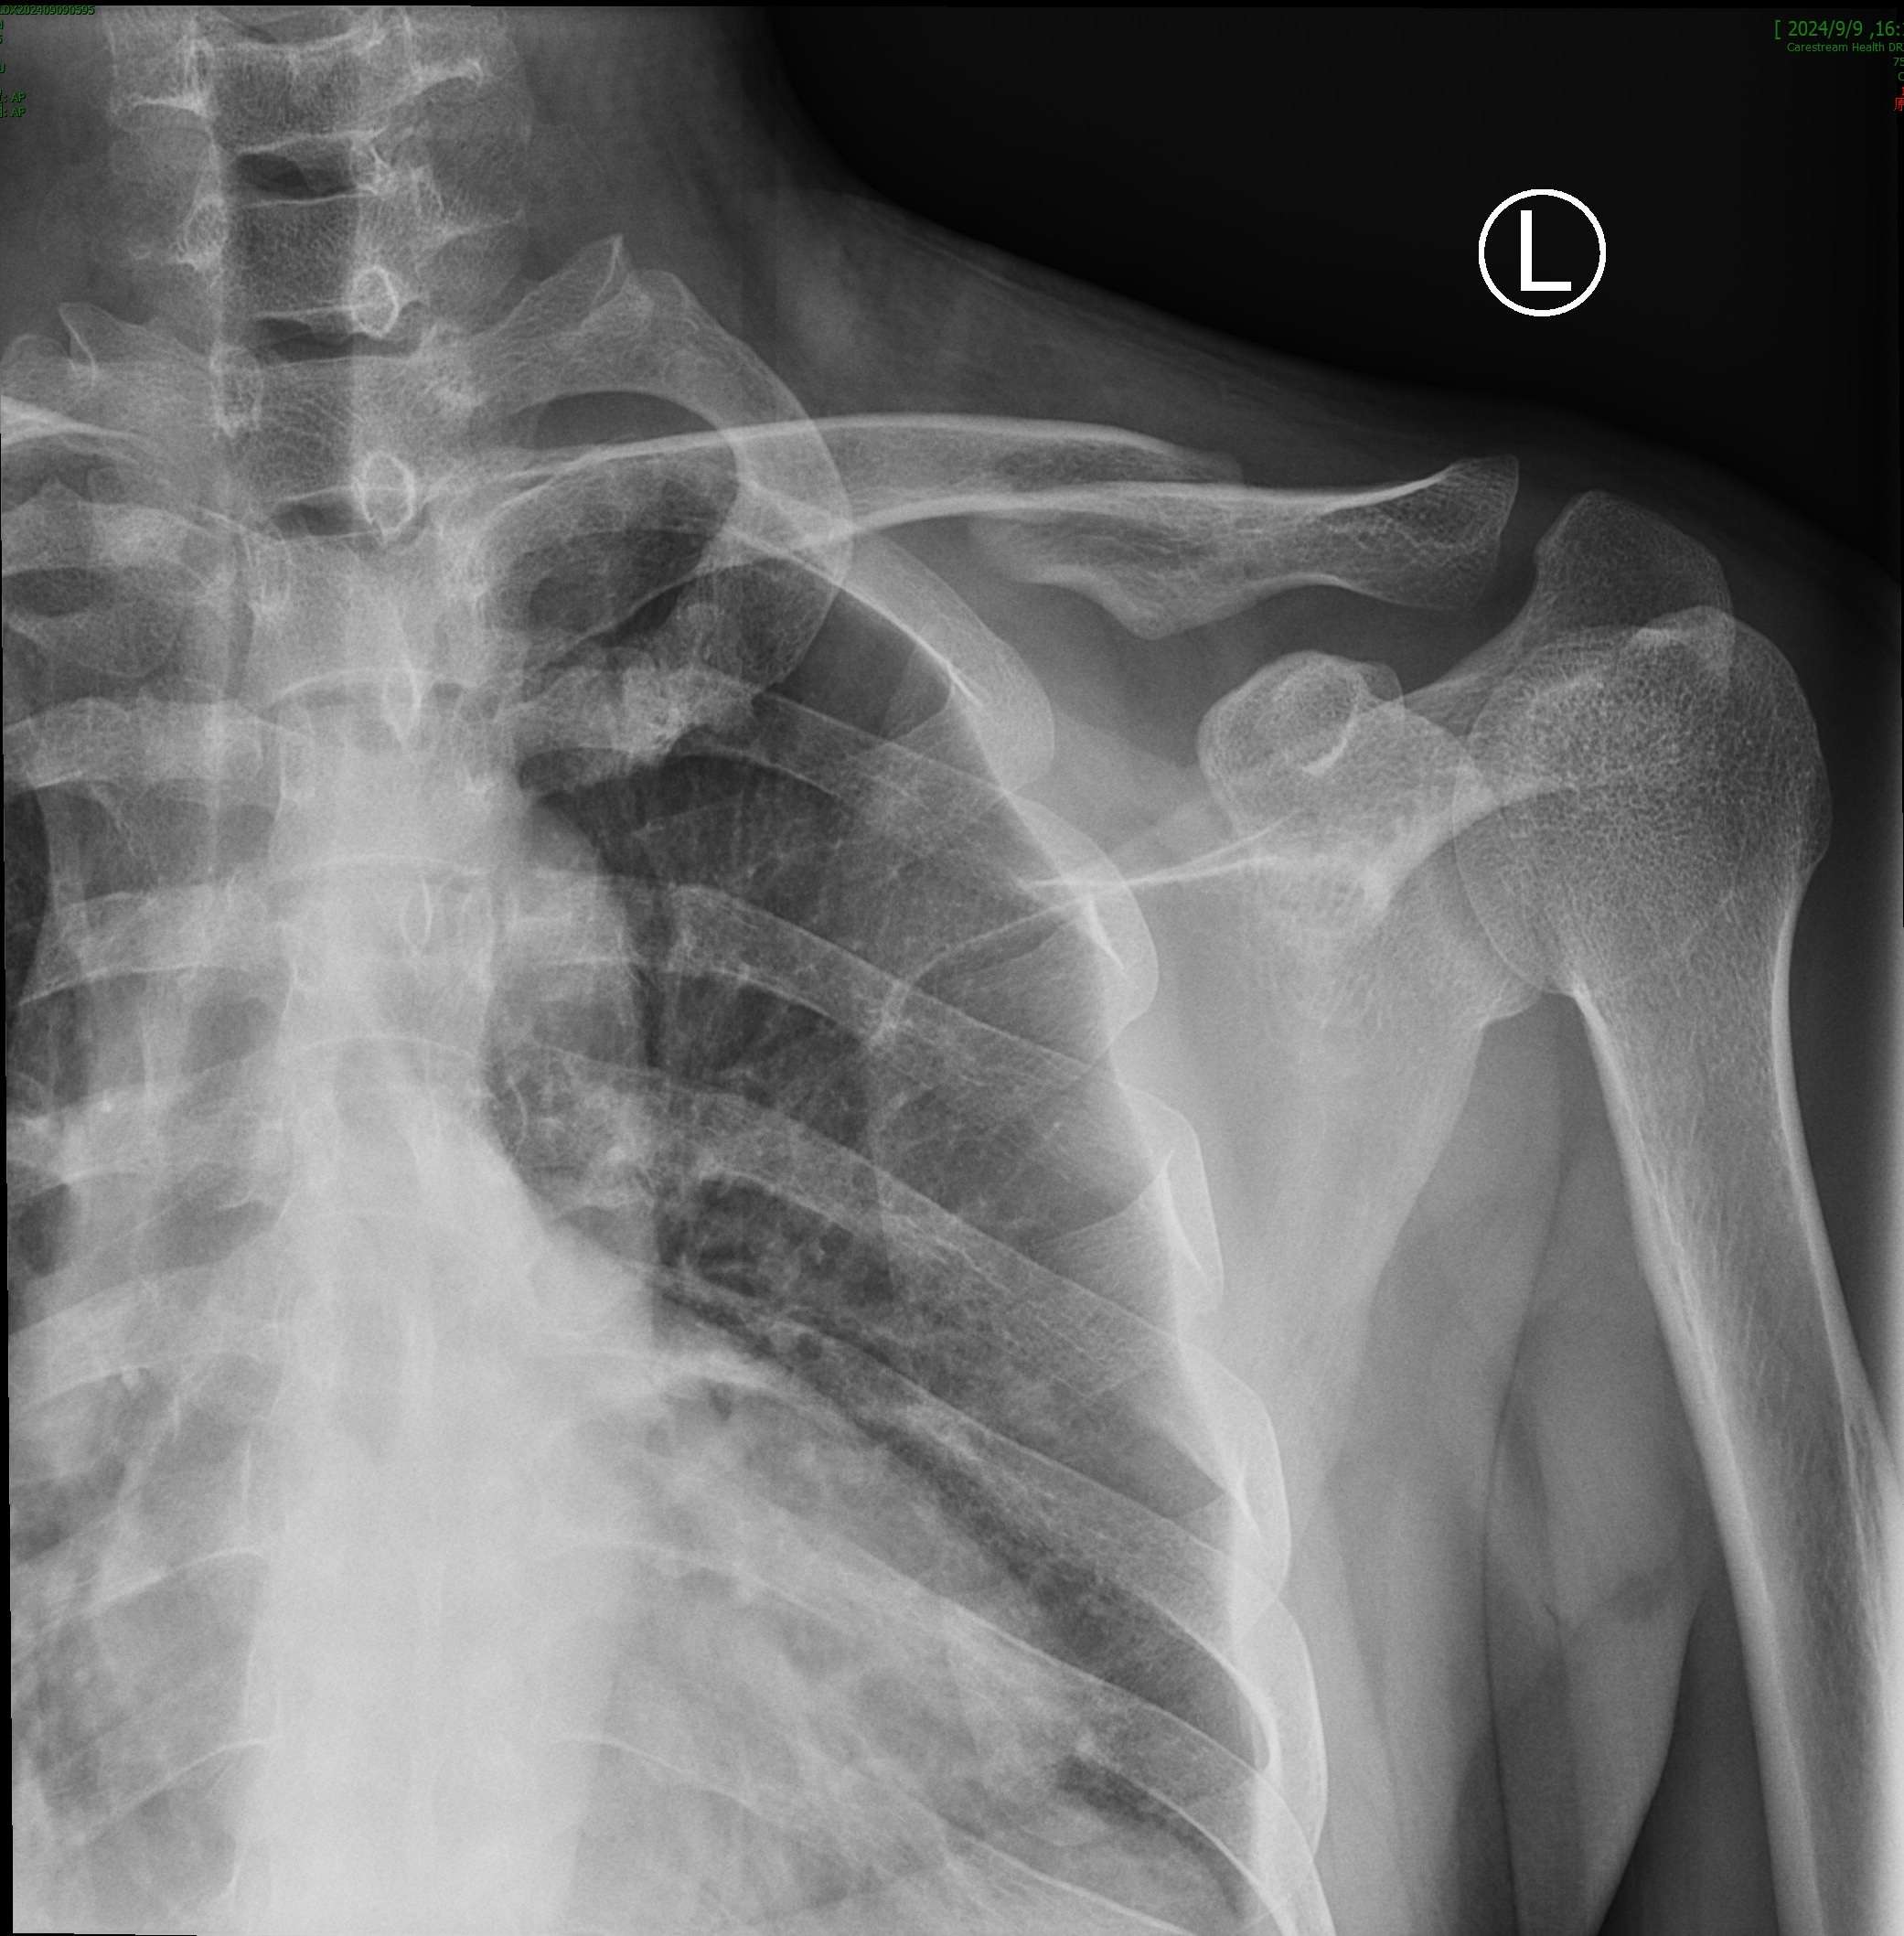

近日,一位36岁男性患者,因骑电动车摔倒,致左肩部肿痛、活动受限,在当地医院检查,拍片显示“左锁骨中段骨折、断端错位明显”,建议手术治疗,患者不想手术,便来到我院手法正骨科就诊。

复位前